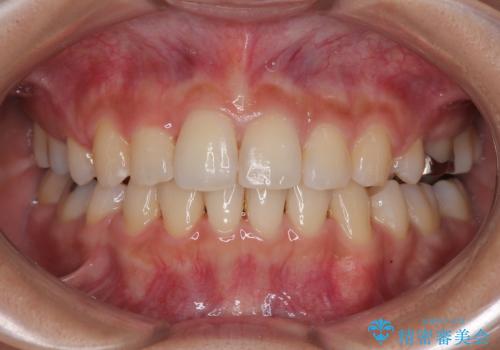

捻れて前に出ている前歯 ワイヤー装置での非抜歯矯正